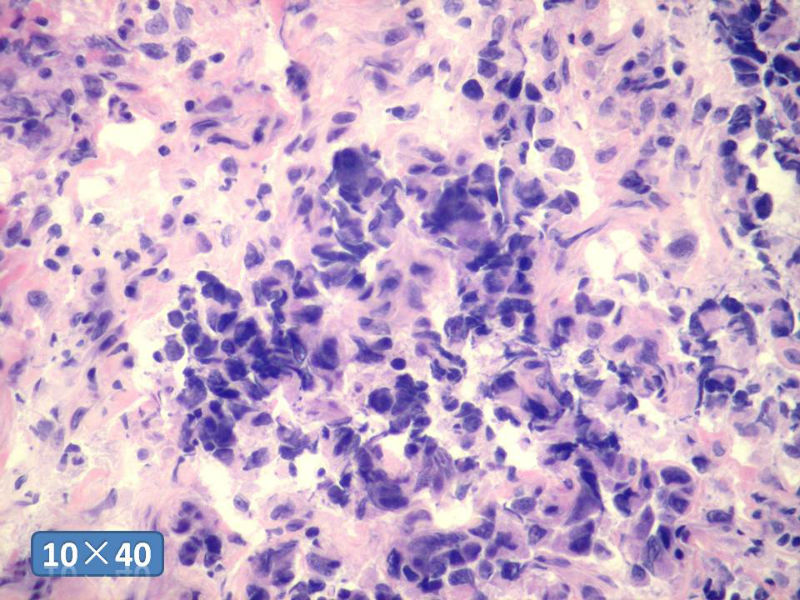

女性,50岁,乳腺肿物,冰冻切片(图1-25)

HE